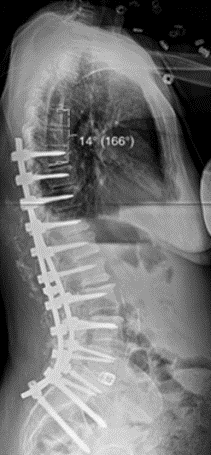

(7)固定棒近端区预弯时考虑因素

图15 近段棒的塑形和近段交界性角度之间的不匹配也是PJK的危险因素之一

因此,术中应顺应脊柱生理弯曲的弧度,尤其在胸腰交界区进行术中特殊弯棒,以避免人为增加交界区应力。